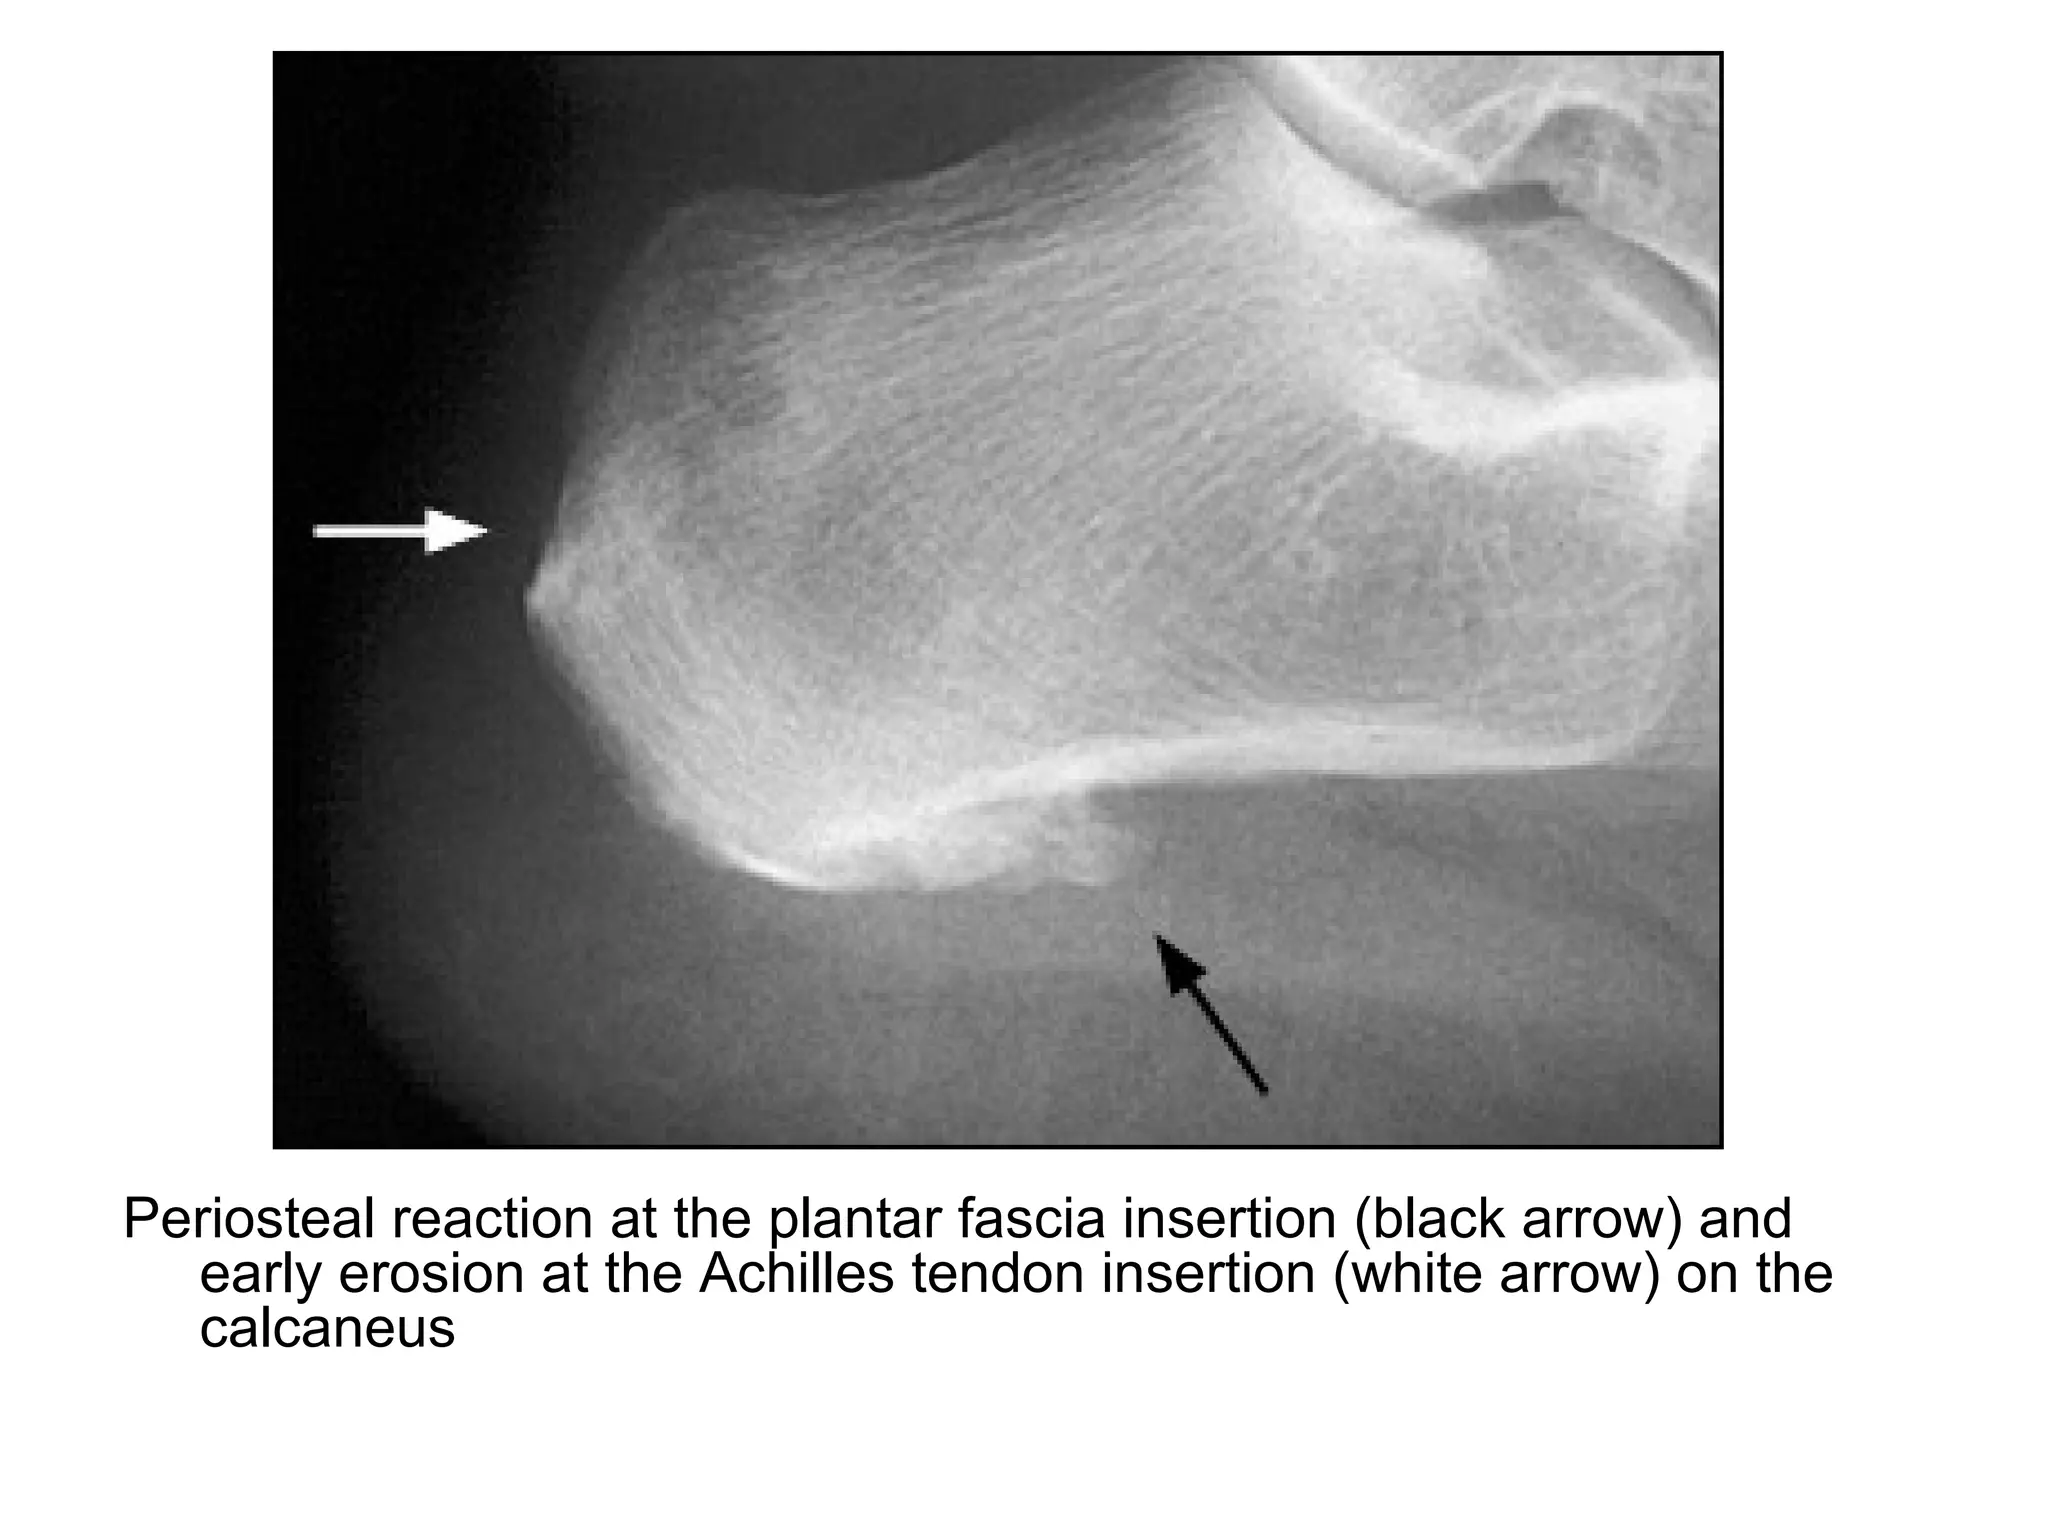

Periosteal reaction at the plantar fascia insertion (black arrow) and

early erosion at the Achilles tendon insertion (white arrow) on the

calcaneus